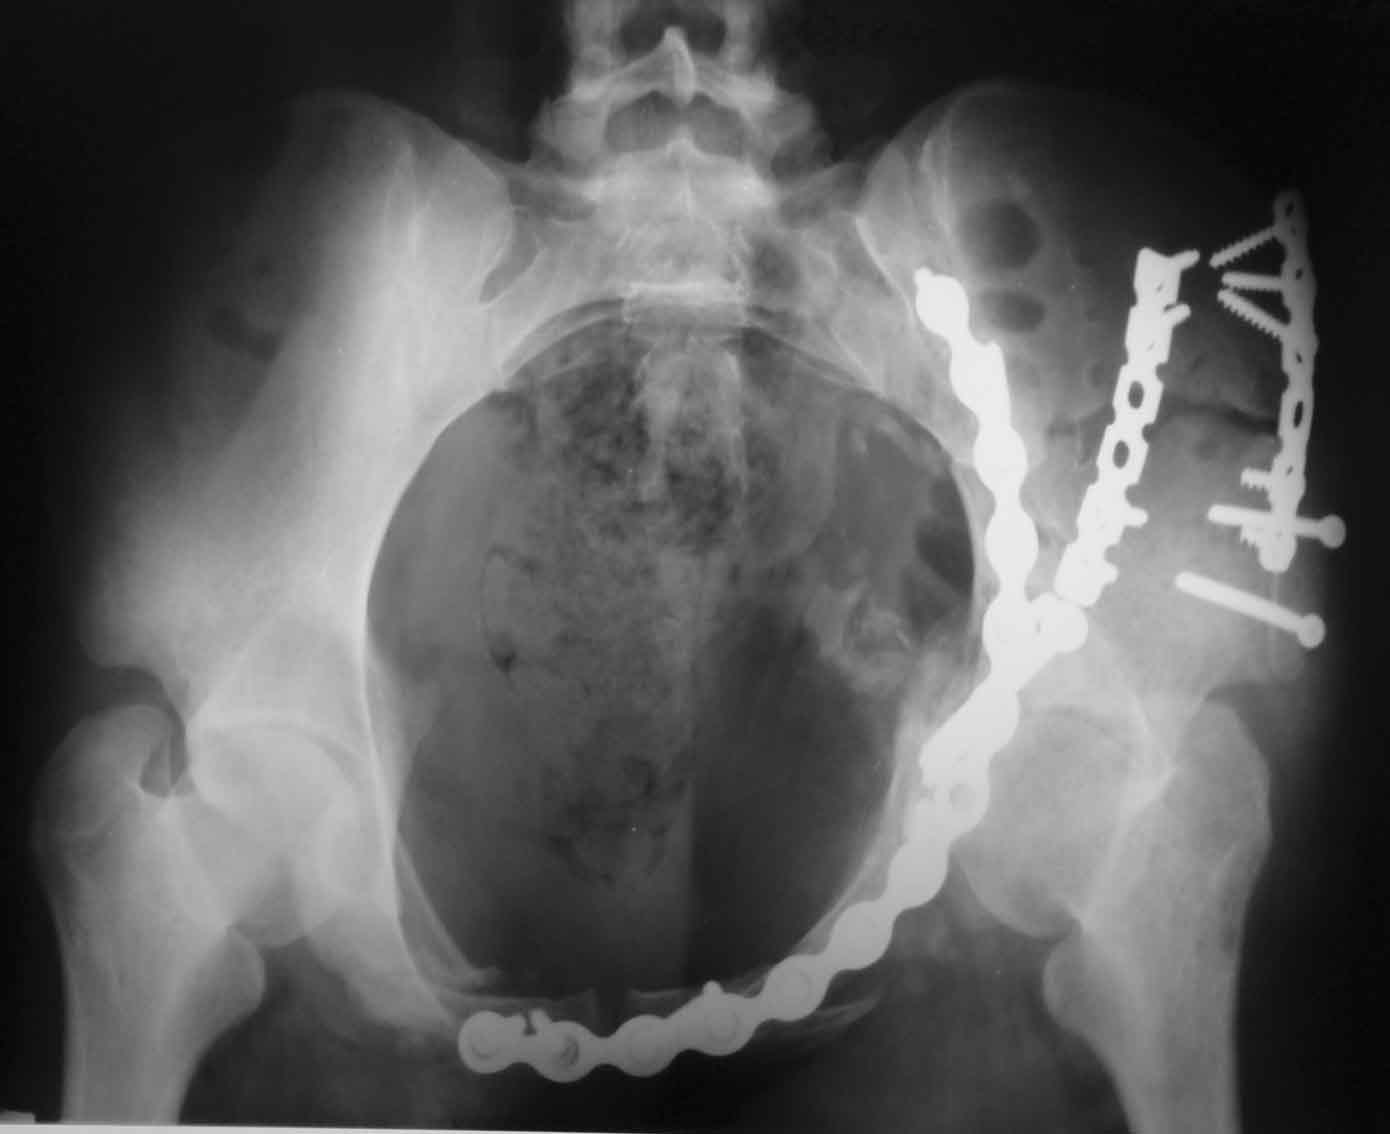

Рентгенограммы после операции

запирательная

A>РО - картина не очень, есть видимость винтов во впадине

По всей видимости, вы имеете в виду канюлированный винт, который проецируется на вертлужной впадине. Та вот, он проведен не через лонную, а седалищную кость. Вертлужная впадина абсолютно интактна. Это хорошо видно на проекции inlet.